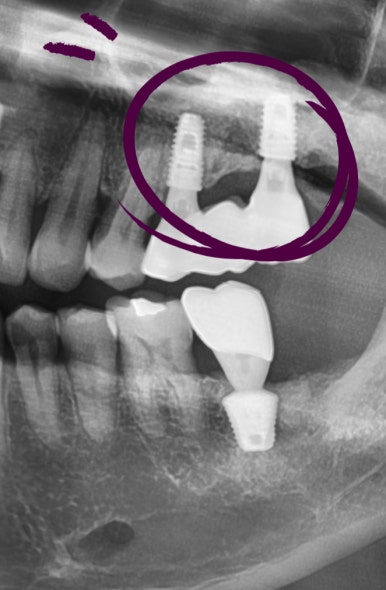

다른치과에서 몇년전에 한 인플란트가 흔들리고 붓는다고 온 분이었습니다.

그림에 1로 표시한 부분은 임플란트 주변을 감싸는 뼈가 많이 녹아서 흔들리고

2로 표시한 치아는 중간 연결고리나사가 부러져서 임플란트 머리도 같이 흔들리는 상태였습니다.

1과 2 임플란트 모두 제거하고

새로 임플란트를 심어 완성하였습니다.